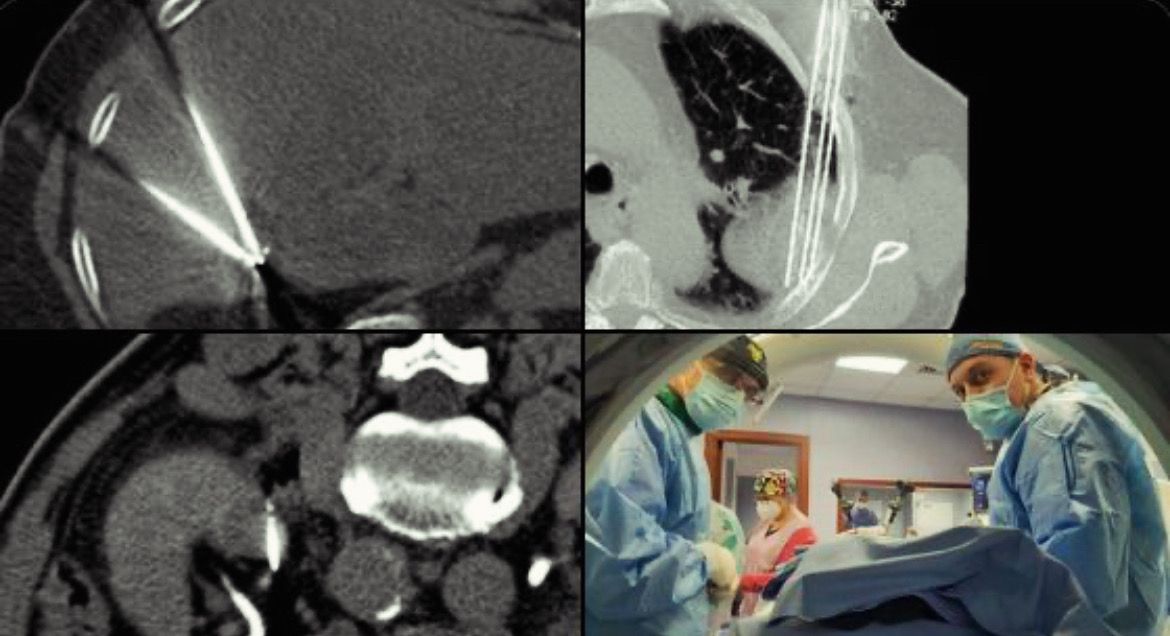

Mi actividad se centra en el tratamiento de tumores malignos óseos y viscerales (hígado, pulmón, riñón, glándulas suprarrenales, entre otros) mediante ablaciones percutáneas con microondas, crioablación, radiofrecuencia o electroporación irreversible (IRE), combinadas cuando es necesario con cementoplastia o fijación percutánea para el control local y la estabilización estructural.